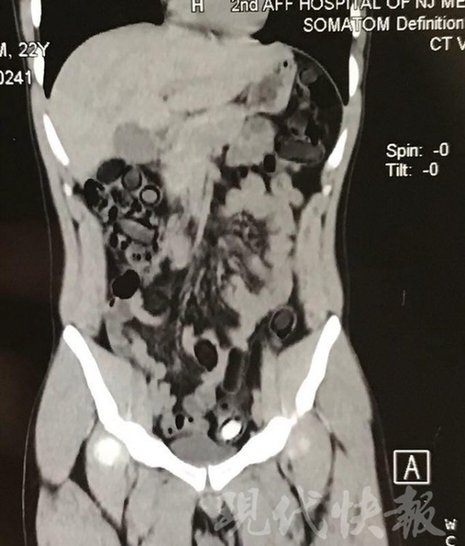

由于毒品在體內(nèi)一旦泄露有可能致命,警方第一時間將阿永帶到醫(yī)院進(jìn)行檢查。CT 掃描的結(jié)果顯示,阿永體內(nèi)布滿了密密麻麻的白色圓柱狀固體,就像一粒粒的蠶蛹。在南京市公安局鼓樓分局二板橋派出所,阿永分四次排出了毒品,毛重369.99克。經(jīng)訊問,阿永交代了自己全部的犯罪事實。目前,阿永已被刑事拘留。